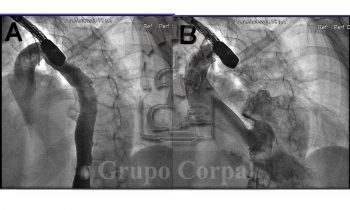

Imágenes mes de marzo 2018, cierre percutáneo de Ductus grande y calcificado en paciente adulto   Imágenes angiográficas de un adulto de 48 años de vida con un gran Ductus Arterioso persistente, con puntos de...